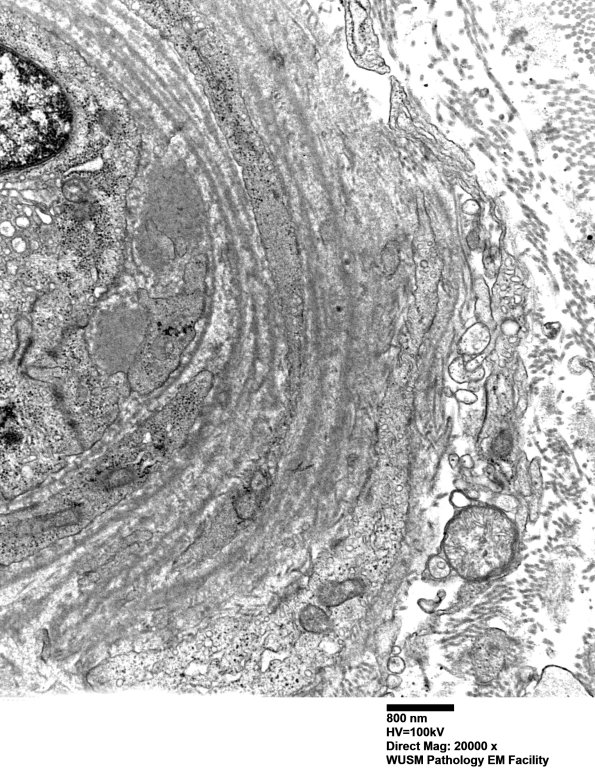

Washington University Experience | VASCULAR | Hypoxia-Ischemia, fetal-neonatal | White Matter | 14B3B (Case 14) EM018 - Copy

14B3B (Case 14) EM018 - Copy